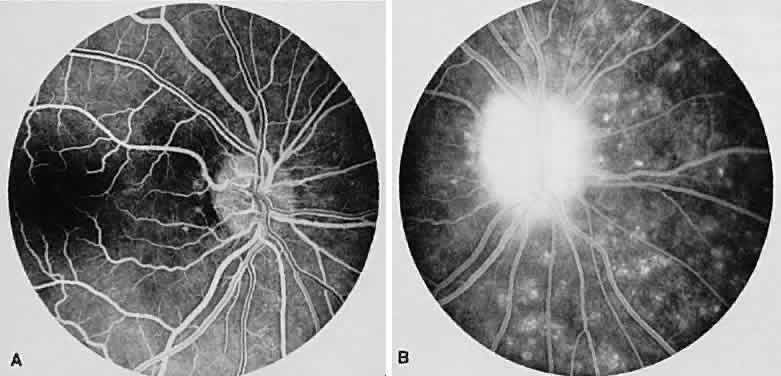

MULTIFOCAL CHOROIDITIS

Multifocal choroiditis may mimic the typical clinical findings of presumed ocular histoplasmosis syndrome (discussed later) and has the additional finding of anterior chamber and vitreous cells. Multiple yellow or gray acute choroidal lesions measuring 50 to 350 μm, periphlebitis, and occasionally retinal neovascularization can be seen. Marked pigmentary disturbances may be seen in the chronic phase (Fig. 11A).

Fig. 11. Multifocal choroiditis. A. Fundus photograph showing pigmentary disturbances. B. Multiple areas of hypofluorescence and hyperfluorescence representing chorioretinal scars with associated atrophic areas. C. Indocyanine green angiogram shows multiple areas of hypofluorescence around the disc, the macula, and the midperipheral fundus. Some of these areas are not visible clinically or on fluorescein angiogram.

On fluorescein angiography (see Fig. 11B), the punched-out lesions show the typical window defects. Acute lesions block early choroidal fluorescence and stain late. Cystoid macular edema and prolonged arteriovenous circulation times may be seen.39 Progressive subretinal fibrosis is a reported sequela that presents as multiple stellar zones of subretinal fibrosis. This fibrosis can be surrounded by multiple atrophic punched-out lesions (Fig. 12).40

Fig. 12. Multifocal choroiditis with subretinal fibrosis in a 26-year-old woman. A and B. Color photographs show hypopigmented lesions representing subretinal fibrosis involving both macular lesions. Multiple punched-out lesions surround the bands of fibrosis. C. Staining of the large stellate fibrous lesion can be seen in the left macula. There are multiple punched-out lesions above and below the macular zone. Leakage from the optic disc and its vessels can also be seen.

ICG angiography shows large hypofluorescent spots in the posterior pole measuring 200 to 500 μm, which did not usually correspond to clinically or fluorescein angiographically detectable lesions (see Fig. 11C). Smaller hypofluorescent spots, less than 50 μm, also may be seen in the posterior pole. Both large and small lesions are best seen in the later phases of the angiogram. Confluent hypofluorescent areas may be seen around the optic nerve in patients reporting an enlarged blind spot on visual field testing.41